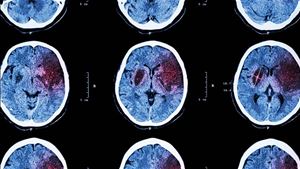

Ela tem 43, ele tem 63. Sofreram ambos um acidente vascular cerebral (AVC) há quatro meses e reconhecem que tiveram sorte. A paragem forçada obrigou Joana e Fernando a viver de uma maneira diferente. O problema atinge cada vez mais pessoas em idade ativa e continua a ser a principal causa de morte e de incapacidade em Portugal. Estima-se que haja 25 mil novos casos de AVC todos os anos. Um em cada três doentes não sobrevive. Quem fica para contar a história nem sempre encontra respostas de reabilitação à medida das necessidades. O Dia Mundial do AVC assinala-se na quarta-feira.

Anualmente, estima-se que, em Portugal, haja 25 mil novos casos de AVC. Um em cada três doentes não sobrevive, o que faz com que esta continue a ser a principal causa de morte e de incapacidade.